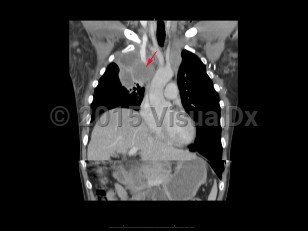

Superior vena cava syndrome (SVCS) results from obstruction of the superior vena cava (SVC), inhibiting venous return from the head, neck, and upper extremities. The most common causes are compression of the SVC due to mediastinal malignancy, followed by thrombosis of the SVC secondary to an indwelling catheter or pacemaker wires. Common symptoms are facial and arm edema, distended neck and chest veins, facial plethora, dyspnea, and cough.

Obstruction of the SVC can cause cervical venous pressures to increase 5-10 times normal. Symptoms usually appear over a period of weeks, and there may be mild improvement as collateral circulation develops. Malignancy is the most common cause, with non-small cell lung cancer and small cell lung cancer making up the majority of cases, followed by lymphoma, metastasis, germ cell cancer, thymoma, and mesothelioma. Thrombosis of the SVC has become more common as the use of indwelling catheters has increased and now contributes to 40% of SVCS cases. Rare causes include benign tumors, aortic aneurysm, thyromegaly, fibrosing mediastinitis from prior irradiation, histoplasmosis, or Behçet's syndrome.

Severity of symptoms depends on the degree of obstruction of the SVC. Facial edema, especially around the eyes; distended neck veins; dyspnea; and cough are common. Signs of cerebral and/or laryngeal edema and cardiorespiratory symptoms are associated with more severe disease and require urgent evaluation. This includes stridor, syncope, headache, vision changes, dizziness, confusion, and obtundation. Esophageal varices are a rare complication, and severity depends on whether the obstruction is proximal or distal to the azygous vein.